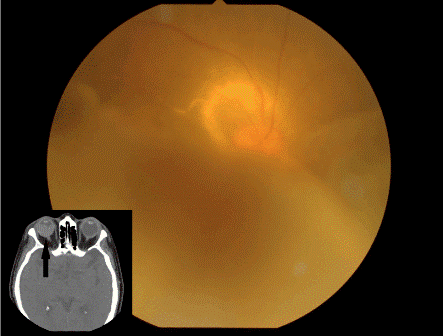

| Figure 3: Six months after initial presentation, fundus photograph of the right eye displays an enlarged choroidal tumor with severe serous retinal detachment. CT reveals a choroidal tumor which occupies the greater part of the vitreous cavity (shown as an inset). |